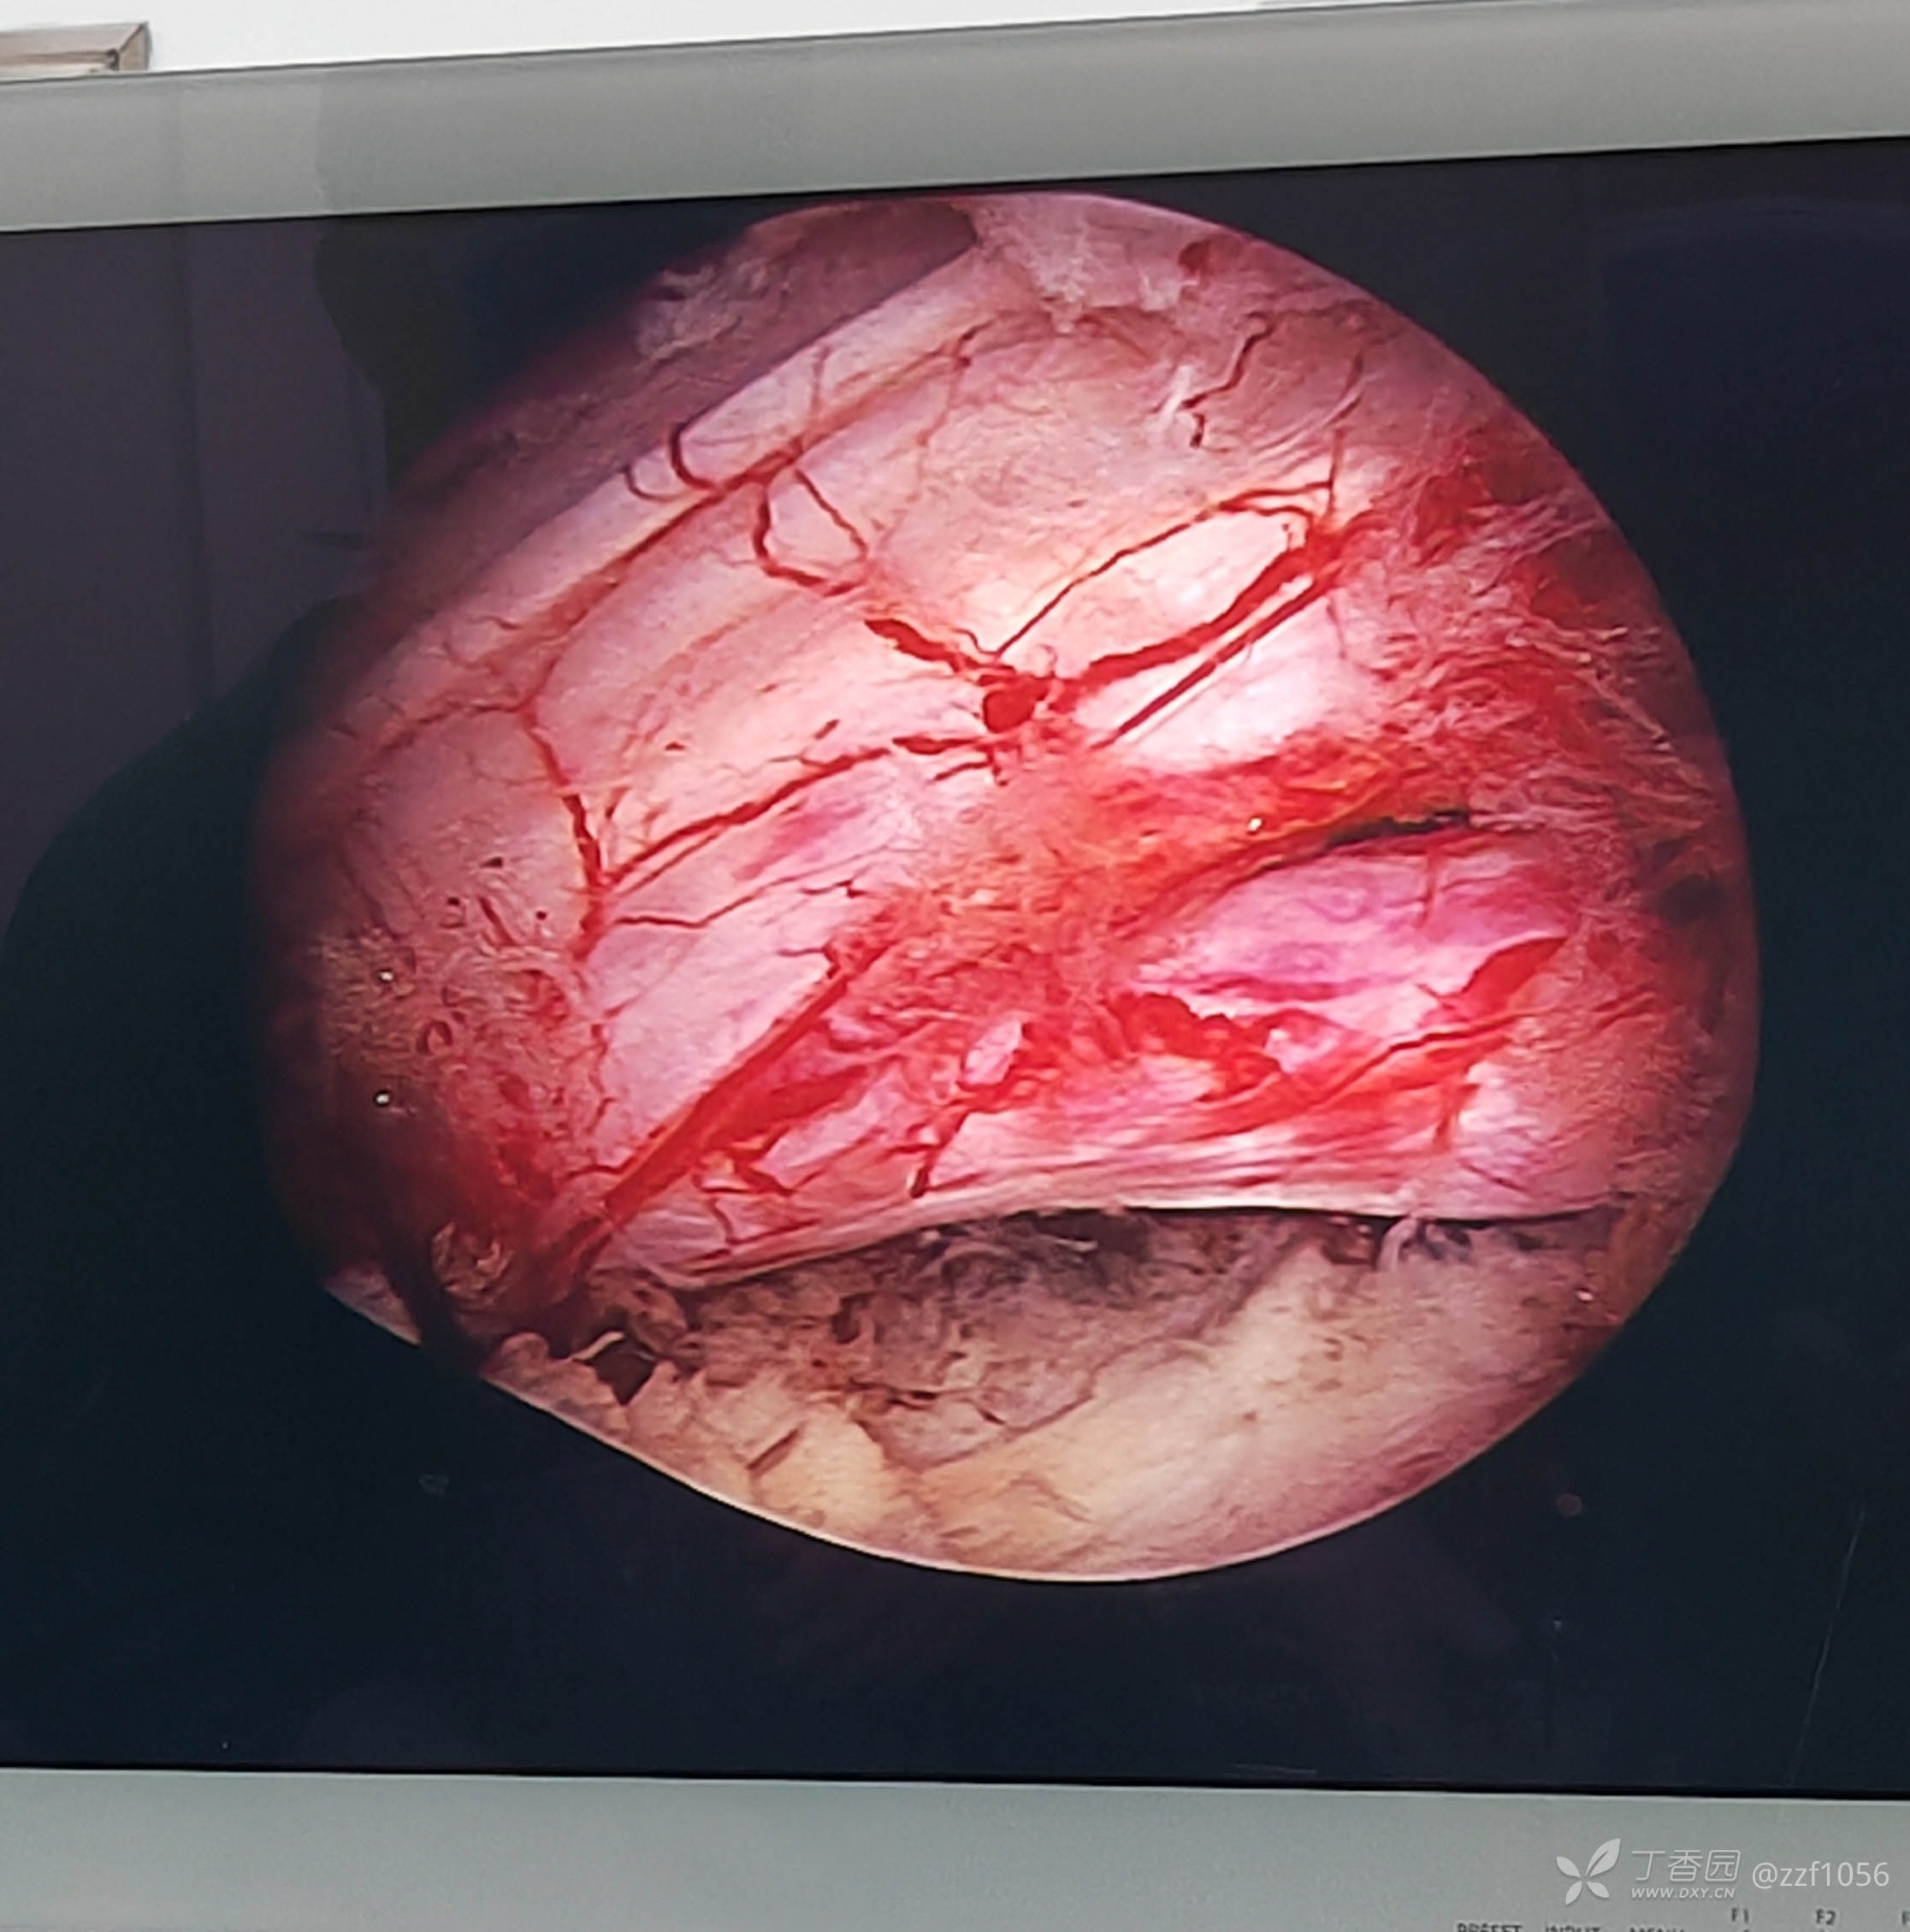

椎板间定位

布坝